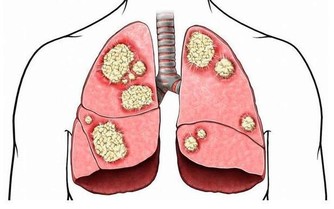

手術治療。大部分的早期黑色素瘤能通過外科手術治療治愈,如果是Ⅰ-Ⅱ期的患者,一般是原發灶手術切除,Ⅲ期患者除了原發灶手術切除,還要做區域淋巴結清掃術,Ⅳ期孤立轉移的患者一般也推薦手術治療。

Ⅰ-Ⅱ期患者治療後5年生存率為98%,中晚期患者的預後效果就不太理想了,分期越高,治療難度越大,預後效果越差,而大部分患者發現時即是中晚期。因此,也提醒大家

免疫治療。免疫治療的出現給黑色素瘤患者的生存期帶來了極大的改善,黑色素瘤患者在十年前普遍生存期不到一年,不到十年的時間裡,由於免疫治療的發展,黑色素瘤逐漸有希望成為一種慢性病,黑色素瘤患者的5年生存期已經上升到50%左右。